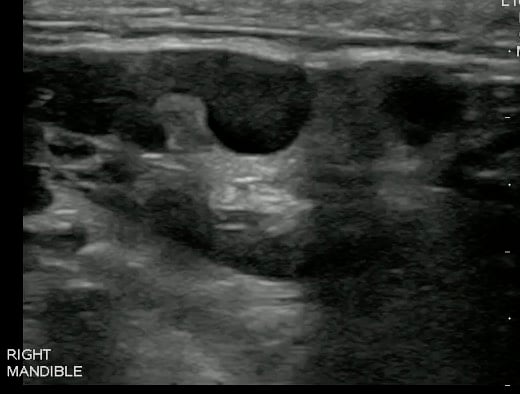

Dental Abscess

- Mandibular Periapical Abscess:

- Figure 7. Mandibular Periapical Abscess

- Although abscesses can have a variety of sonographic appearances, the most common appearance is that of a hypoechoic mass relative to adjacent structures, or entirely anechoic.

- It can appear as a complex mass with scattered echoes that represent necrotic debris or tissue.

- Abscess cavity may contain septae or gas within it.

- Color Doppler may demonstrate hyperemia around the abscess cavity and absence of flow within it.